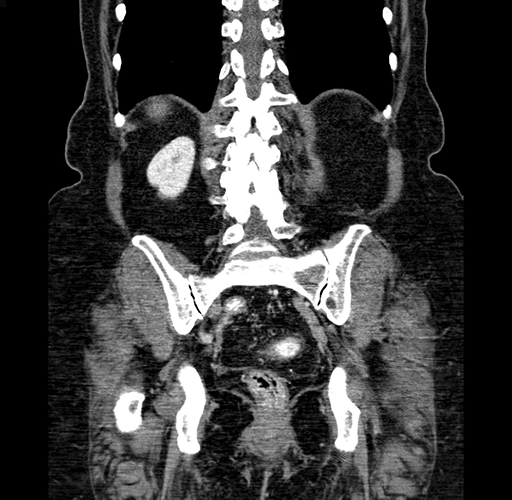

Pre-Chemo: Coronal Venous

Coronal Venous